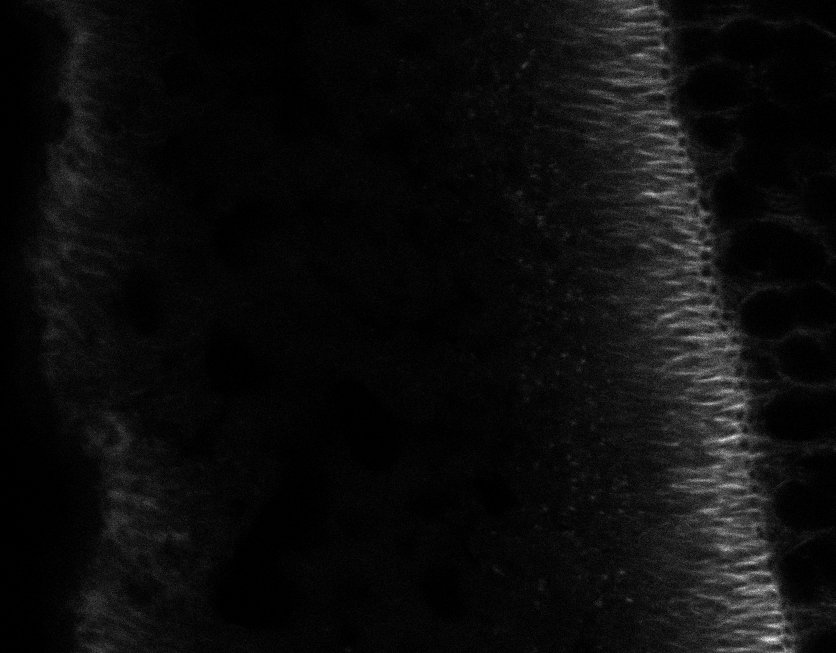

Healthy Retina

Unhealthy Retina